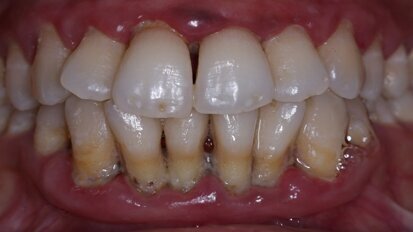

Allogenic stem cells – a faster and cheaper method to treat periodontitis

SENDAI, Japan: Periodontitis is a common oral disease that affects the oral health of many people with serious effects. A new research from Japan proposes a...